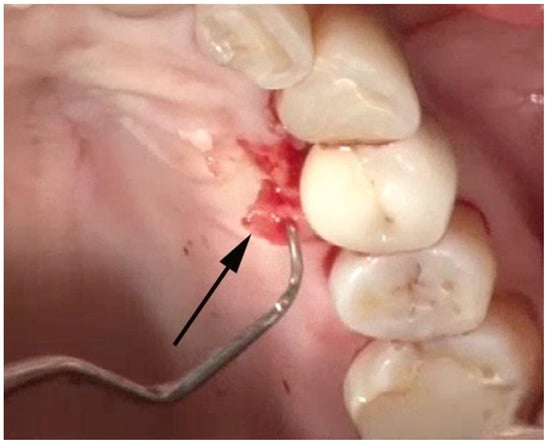

Figure 7. A thin (1–2 mm) section of tissue (arrow) containing foreign particles of titanium or cement is removed from the area of bone loss.

Once the implant has been adequately visualized, under videoscope guidance and using a new small blade, a thin section of tissue approximately 1–2 mm in thickness is removed from the tissue that was in contact with the implant in the area of bone loss. (Figure 7) When this tissue is evaluated histologically, as was done in the study by Wilson et al., multiple areas of cement and/or titanium particles surrounded by inflammatory cells are often noted. The purpose of removing this tissue is to eliminate foreign material that may cause further damage to the implant-supporting bone in the future as well as may interfere with the regeneration of bone around the implant.